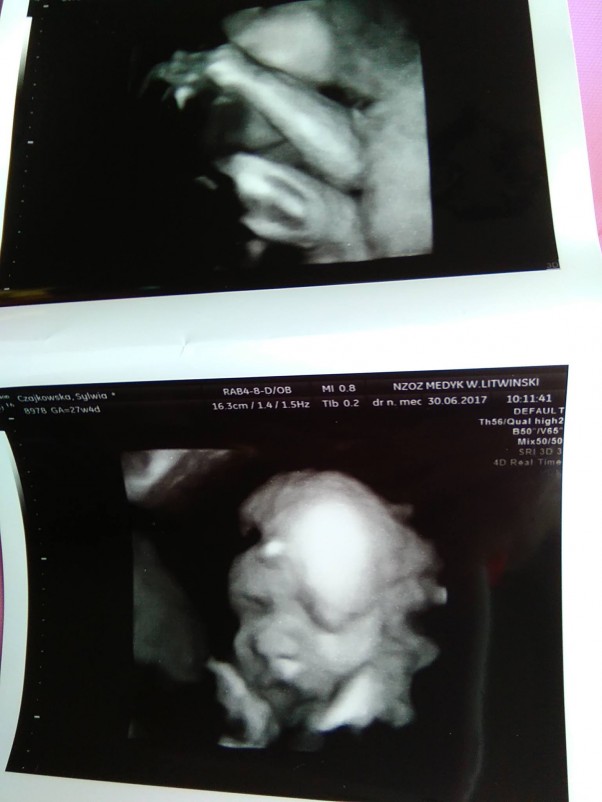

917 g szczęścia

My właśnie dotarłyśmy do domku po wizycie u ginekologa mamy prawie kg :-)